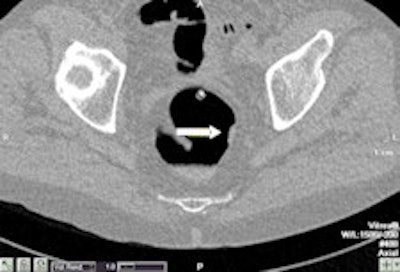

Example of a test case with two subtle rectal lesions in the rectum. Left: The small 7-mm polyp was detected by four out of five readers. Right: The 1-cm lesion with flat morphology was detected by all readers. This lesion was a flat cancer. Images courtesy of Dr. Philippe Lefere."The same radiographers were further evaluated in a larger study, also with good results," said co-author Dr. Philippe Lefere, a radiologist at Stedelijk Ziekenhuis in Roeselare, Belgium. "The program is conceived so that the novices perform the 75 examination themselves, and this allows them to learn the technique. We supervise each examination, and afterwards they are tested."